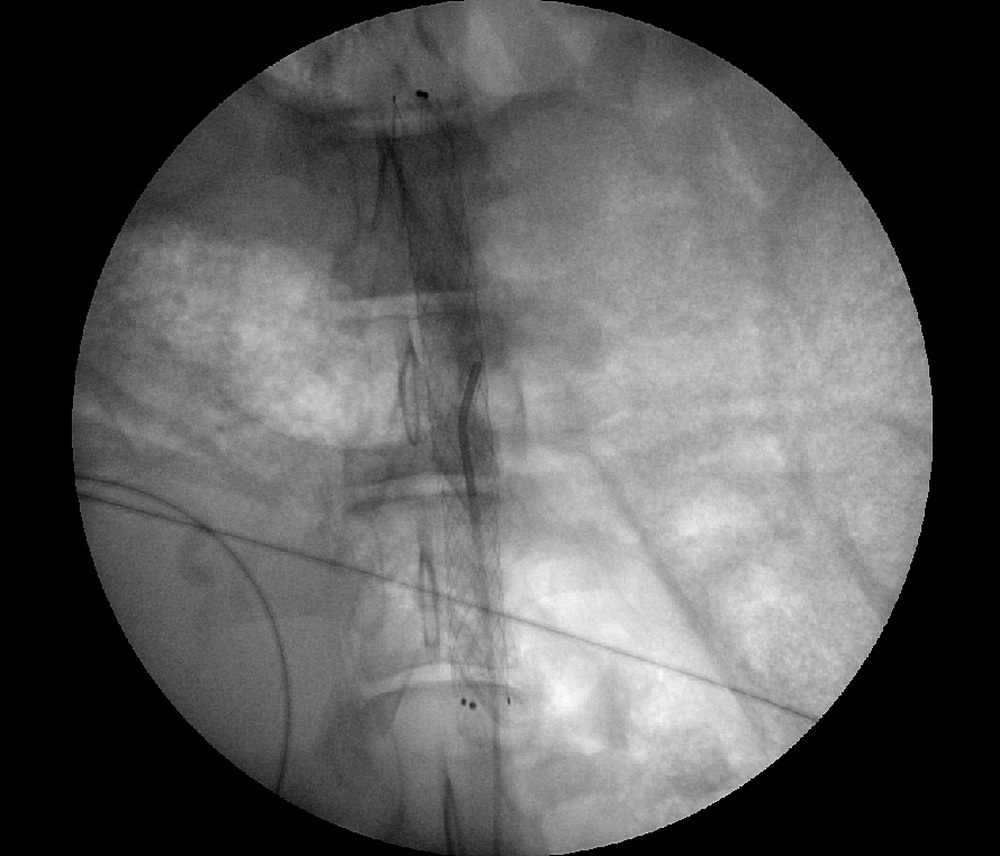

В Центре Алмазова на базе Центра доклинических и трансляционных исследований (ЦДТИ) под руководством д.м.н. М. А. Чернявского уже второй год ведется активная работе по теме проекта. Совместно с участником Медицинского научно-образовательного кластера «Трансляционная медицина» научно-производственным комплексом «Ангиолайн» разработаны опытные образцы голометаллических стентов, которые имплантированы двум экспериментальным животным (минипигам). Стоит отметить, что первому животному, которому выполнена имплантация стента на уровне почечных артерий, через 3 месяца проведена контрольная ангиография с положительным результатом – стент и почечные артерии проходимы. Это первый в Центре Алмазова хронический эксперимент с таким длительным периодом наблюдения — более 5 месяцев!

Контрольная ангиография через 3 месяца после имплантации стента первому животному